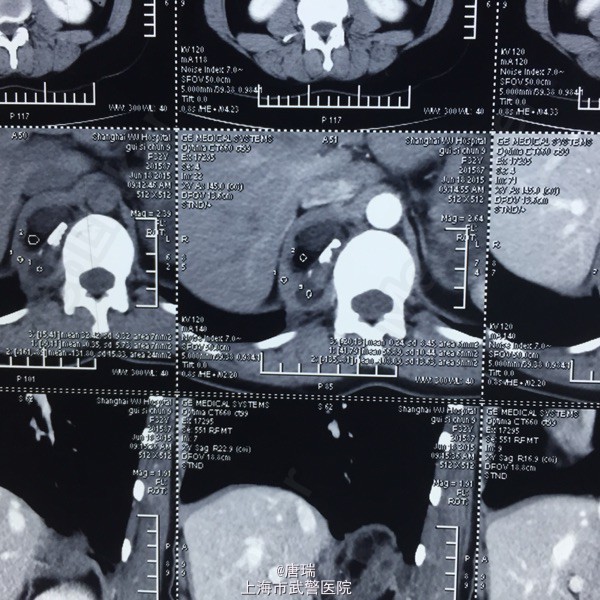

腹膜后占位,错构瘤与畸胎瘤的鉴别

畸胎瘤

体检发现脊柱旁腹膜后占位。